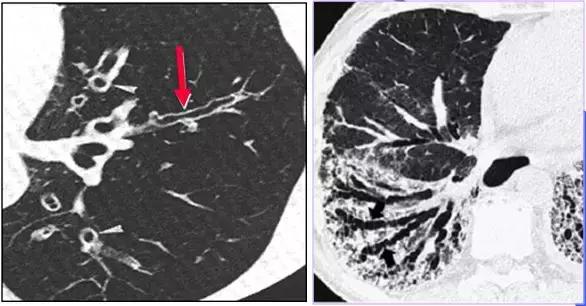

CT征象七:马赛克灌注

马赛克灌注(Mosaicperfusion)

在HRCT上,由于气道疾病或肺血管性疾病引起相邻的肺区血液灌注上的差别而出现的不均匀肺密度区,称马赛克/镶嵌性灌注。常见于造成局部气体滞留或肺实质通气不良疾病中 。

HRCT示略高密度磨玻璃密度影和低密度马赛克灌注区

由于气体储留引起的马赛克灌注

小气道病变引起两侧肺的马赛克灌注

小气道病变引起两侧肺的气体潴留